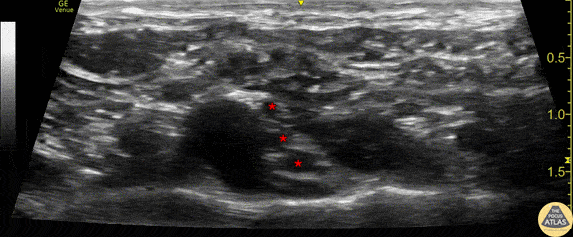

Anatomy of the supraclavicular brachial plexus. This image was obtained with the linear transducer in a parasagittal orientation just lateral to the neck. Left of image is anterior in this view. The brachial plexus (*) is seen just posterior to the pulsating subclavian artery. The hyperechoic first rib can be seen just below the artery and brachial plexus. Drs. Sam Paskin-Flerlage, PGY4 and Michael Heffler, PGY3 Denver Health Residency in Emergency Medicine